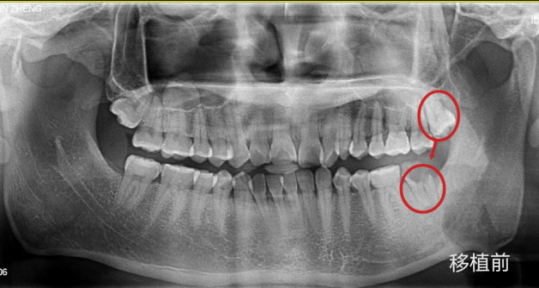

变废为宝!带你了解自体牙移植

自体牙移植,是指利用自己的牙齿(智齿、正畸需要拔除的牙等)来替代因为龋坏、外伤或者肿瘤侵犯而无法保留需要拔除的患牙。临床上最常见的自体牙移植来源是我们的第三磨牙,即智齿。

1.确定“坏牙”和用来替代的智齿;

2.拔掉“坏牙”和智齿;

3.将智齿种在原“坏牙”处;